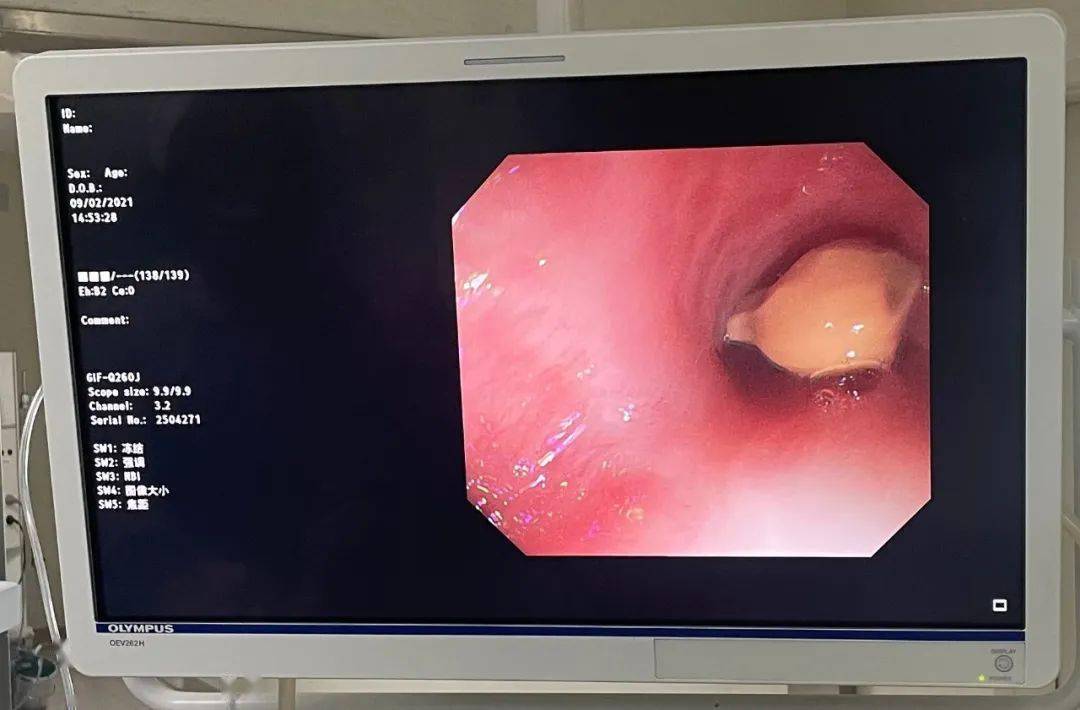

瓶盖取出后所见的缺血食管黏膜

图片尺寸1171x1010